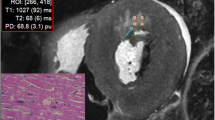

A commercially available post-processing tool (SyMRI Autopsy, SyntheticMR, Linköping, Sweden) [22] was used to measure the T1 and T2 relaxation times and PD by placing five ROIs in organs (myocardium, liver, spleen) and tissues (subcutaneous fat and pectoralis muscle) covered on cardiac short axis images (Fig. 2). T1 and T2 relaxation times in milliseconds (ms) as well as the PD (%) were plotted in a 3D plot using the ThreeDifyExcelGrapher add-in for Microsoft Excel® to investigate clustering and separation of organs and tissues. Two-way analysis of variance (ANOVA) was carried out to look for significant differences of quantitative T1, T2 and PD values between all organs/tissues. The null hypothesis was rejected when the p value was less than 0.05.